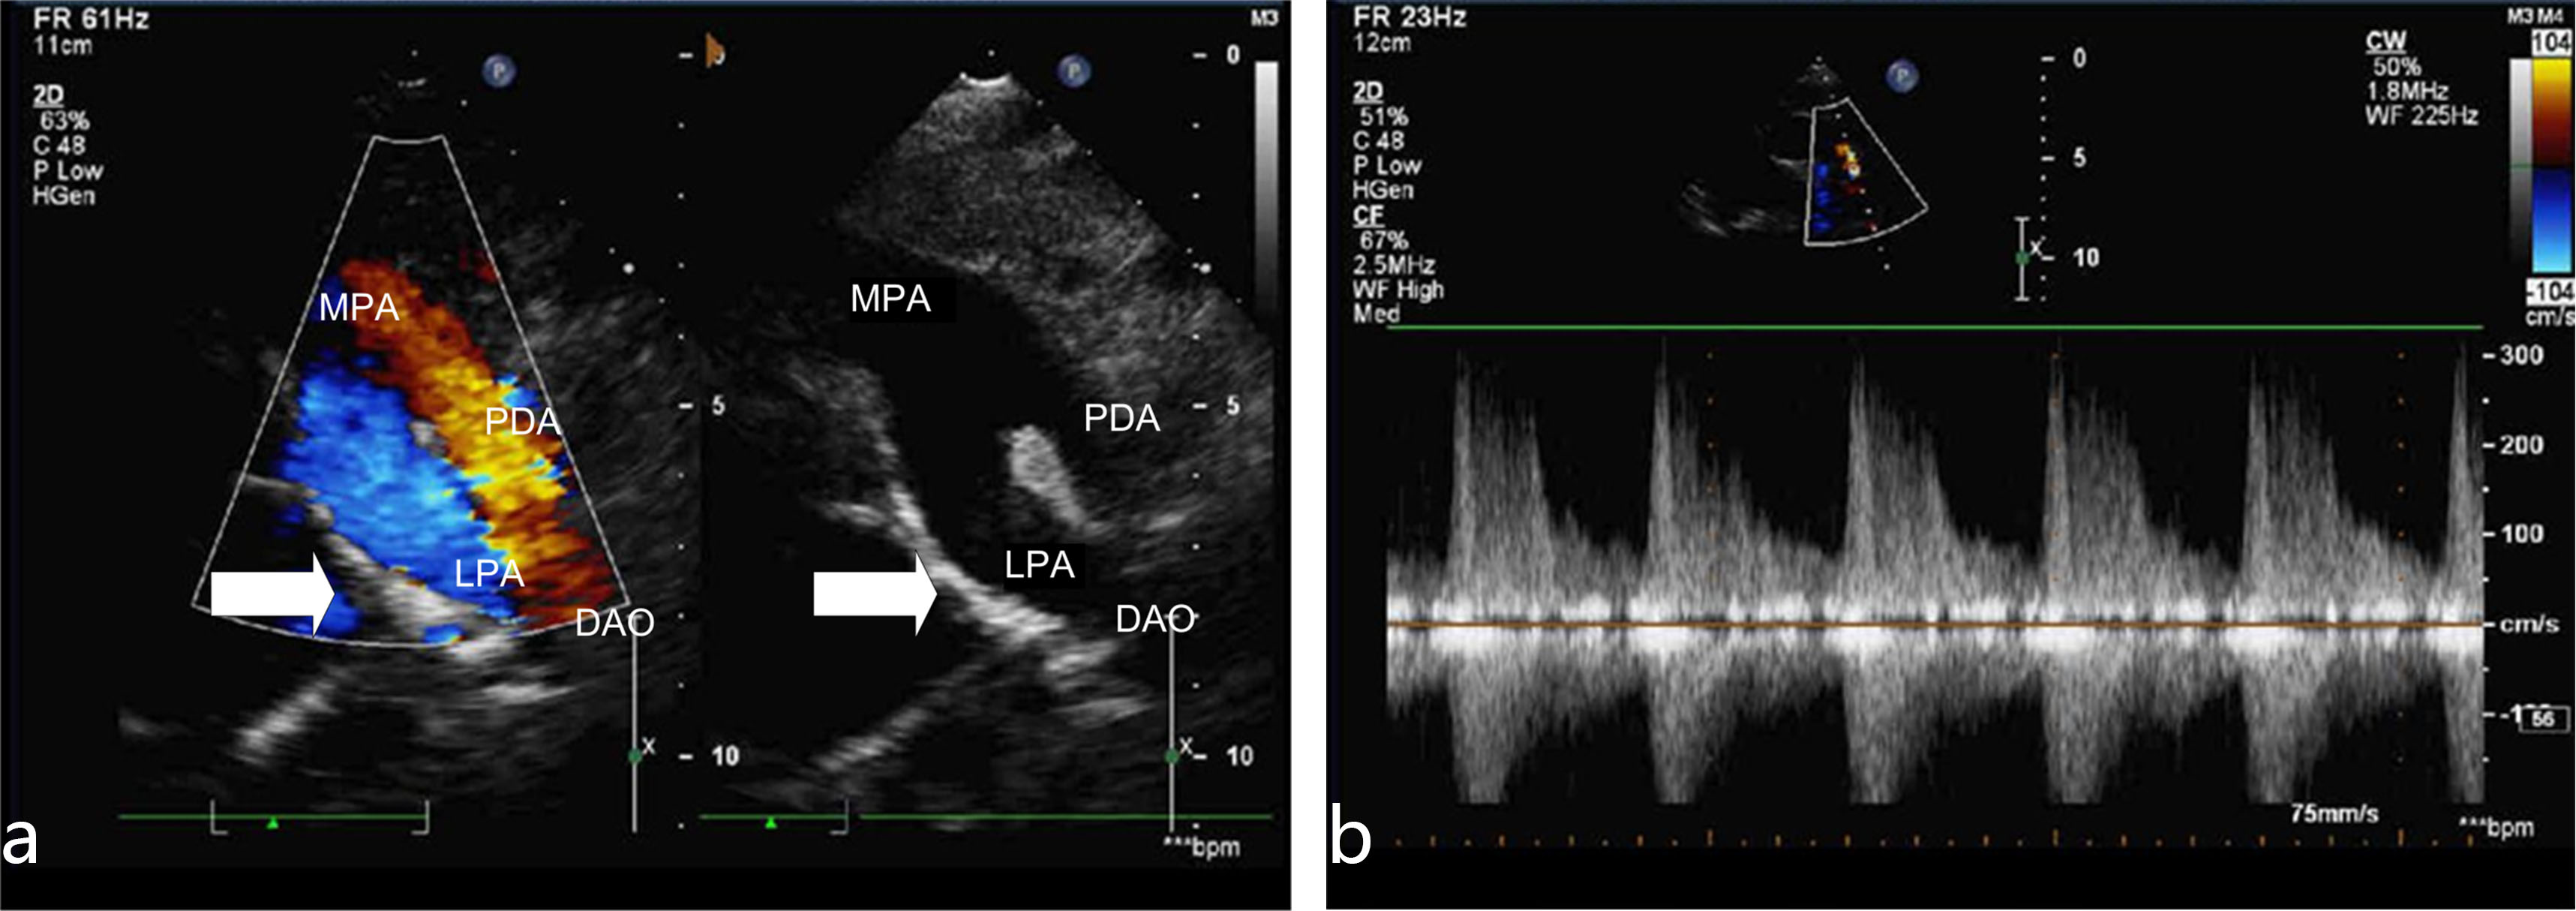

The absence of right pulmonary artery combined with single ventricle and endocardial cushion defect. There is no right pulmonary artery structure in the trunk of pulmonary artery as shown in Figs. 2,3 (hypertension group). The regurgitation peak velocity (Vmax) was 411 cm/s and pressure gradiant (PGmax) was 67 mmHg (means the mean pulmonary arterial pressure is estimated to be 67 mmHg). There is no normal ventricular septal structure in the ventricular cavity. The left and right atrium communicated with the common ventricle through the common atrioventricular valve; Combined with partial endocardial cushion defect: the normal crisscross structure between atrioventricular septum and atrioventricular valve disappear, and the echo below the atrial septum is lost.

Fig. 2.Right pulmonary artery absence with single ventricle. (a) Suprasternal long axis view (2D image). In this view there is not right pulmonary artery structure from the main pulmonary artery (arrow). LPA, left pulmonary artery. (b) High level parasternal view (2D image). In this view there is only left pulmonary artery structure from the main pulmonary artery (arrow). LPA, left pulmonary artery; MPA, Main pulmonary artery.